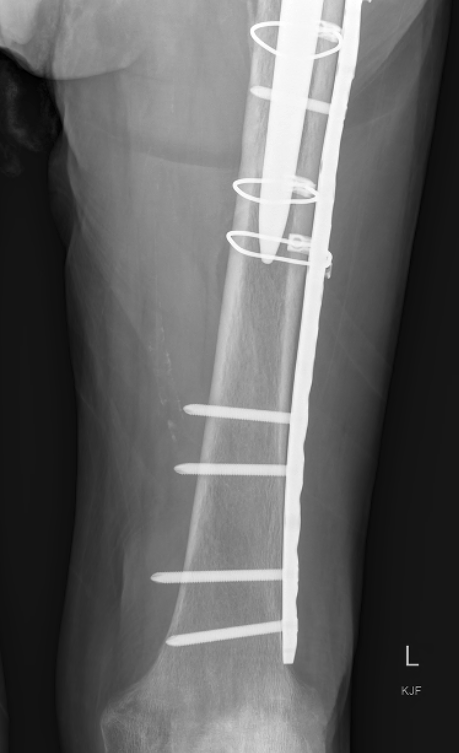

Revision uncemented arthroplasty with Zimmer cable plate

ORIF Locking cable plate +/- cortical strut allograft

- overlap femoral implant

- to distal femur